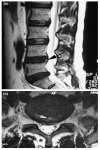

Discogenic lower back pain (DLBP) is the most common type of chronic lower back pain (LBP), accounting for 39% of cases, compared to 30% of cases due to disc herniation, and even lower prevalence rates for other causes, such as zygapophysial joint pain. Only a small proportion (approximately 20%) of LBP cases can be attributed with reasonable certainty to a pathologic or anatomical entity. Thus, diagnosing the cause of LBP represents the biggest challenge for doctors in this field. In this review, we summarize the process of obtaining a clinical diagnosis of DLBP and discuss the potential for serum-based diagnosis in the near future. The use of serum biomarkers to diagnose DLBP is likely to increase the ease of diagnosis as well as produce more accurate and reproducible results.